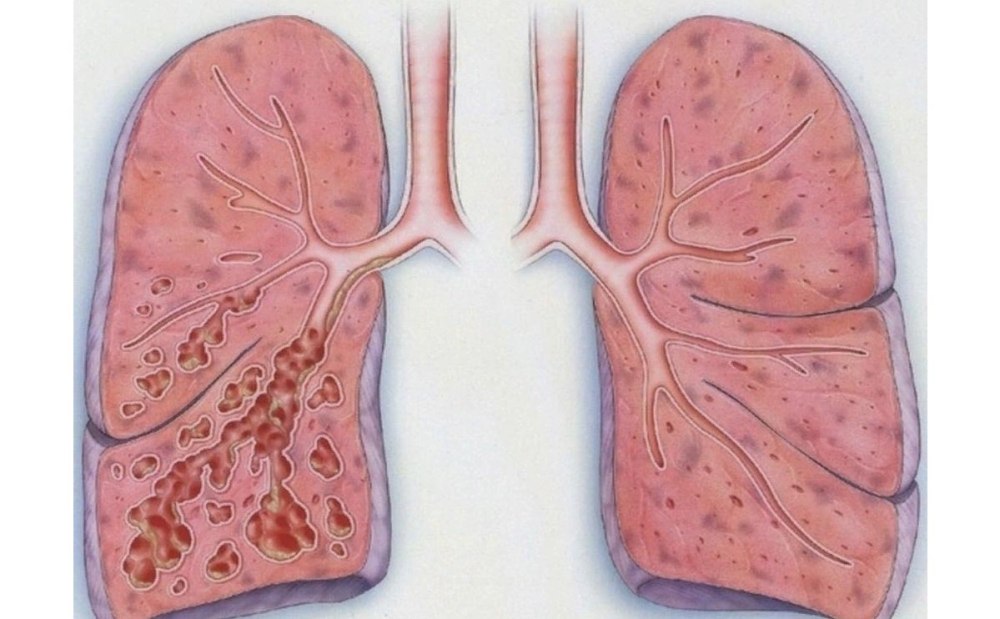

Дыхательная гимнастика при пневмосклерозе: техника и советы